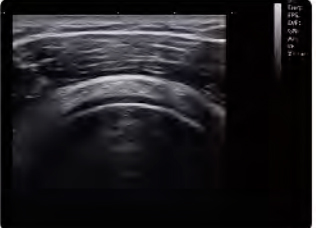

Du point de vue du professionnel de la santé, l’échographie constitue un outil de plus en plus indispensable au développement d’une physiothérapie efficace. L'échographie offre au physiothérapeute la possibilité d'étudier le corps humain de manière exhaustive. Une étude dynamique, précise, non invasive et en temps réel qui offre de nombreux avantages tant pour le professionnel que pour le patient.

Dans le domaine de la physiothérapie, l’échographie devient une extension du professionnel. Une aide précieuse pour évaluer et diagnostiquer objectivement le tissu neuromusculo-squelettique, pour mieux planifier le traitement à suivre, évaluer l'évolution de la blessure et valider les différentes techniques de physiothérapie thérapeutique, améliorant ainsi le succès des thérapies.

L'appareil CBit 6 réinvente les termes d'efficacité et de précision au sein des échographes moyen-haut de gamme car il est équipé de la technologie de dernière génération. De cette manière, l’équipement parvient à capter des échos beaucoup plus précis puisqu’il est équipé de processeurs de transmission plus puissants et d’une réception du signal plus fluide.